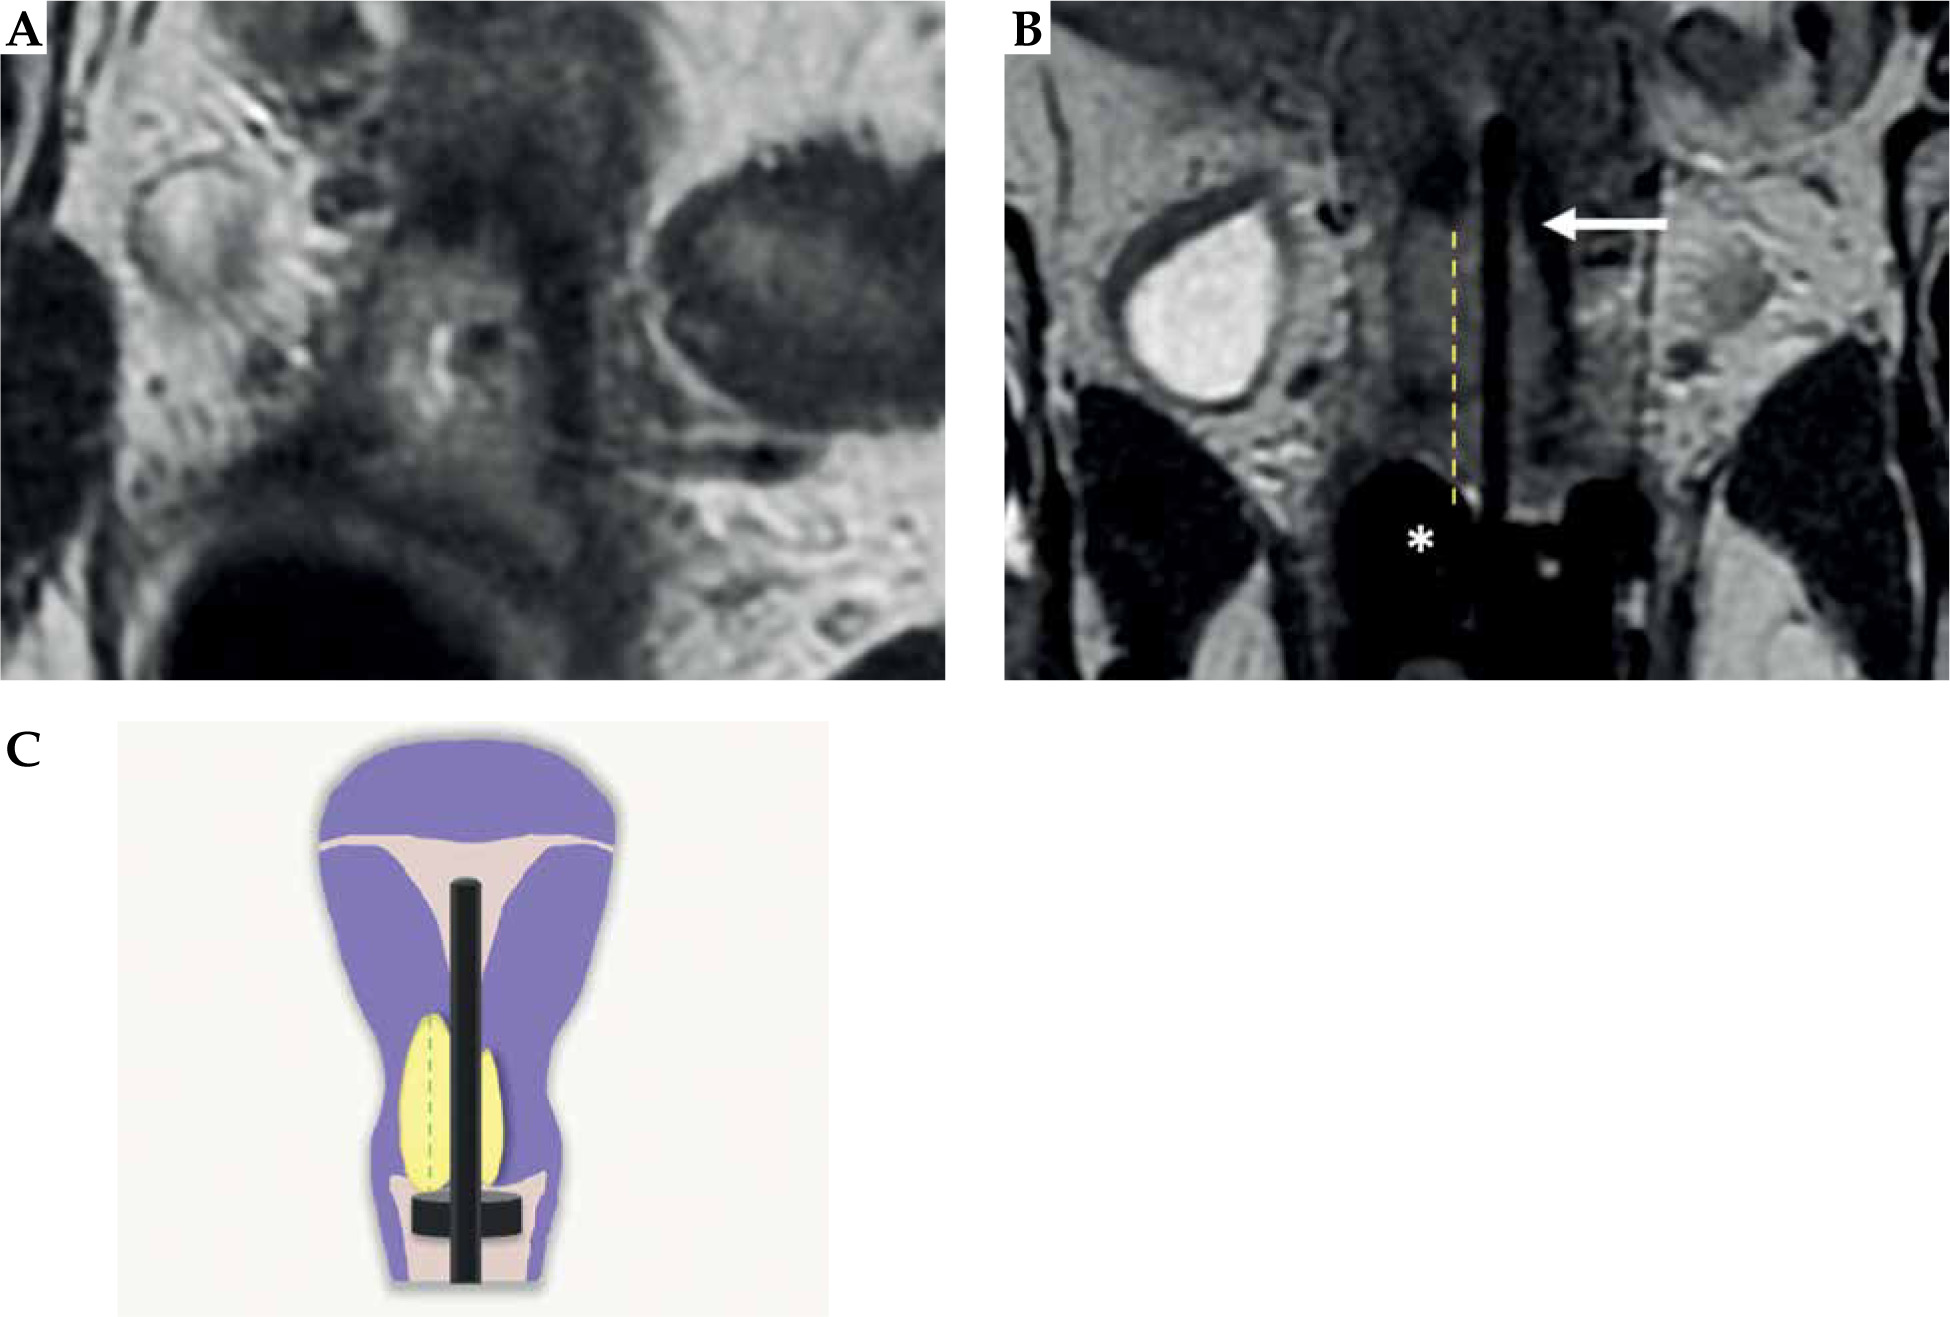

Fig. 8

Tumor maximum thickness: axial oblique T2-weighted FSE image perpendicular to the plane of the applicator (A) shows tumor extension within cervical stroma (arrow with maximum tumor extension (dotted line) from the tandem (arrowhead) within the cervical stroma at 9 o’clock) (B). Schematic illustration of the tumor maximum thickness (C)

Fig. 9

Maximum tumor length: coronal oblique T2-weighted FSE image in the plane with the applicator (A) shows maximum tumor length (dotted line) from the ring (*), along with the tandem (arrow) (B). Schematic illustration of the tumor maximum thickness (C)